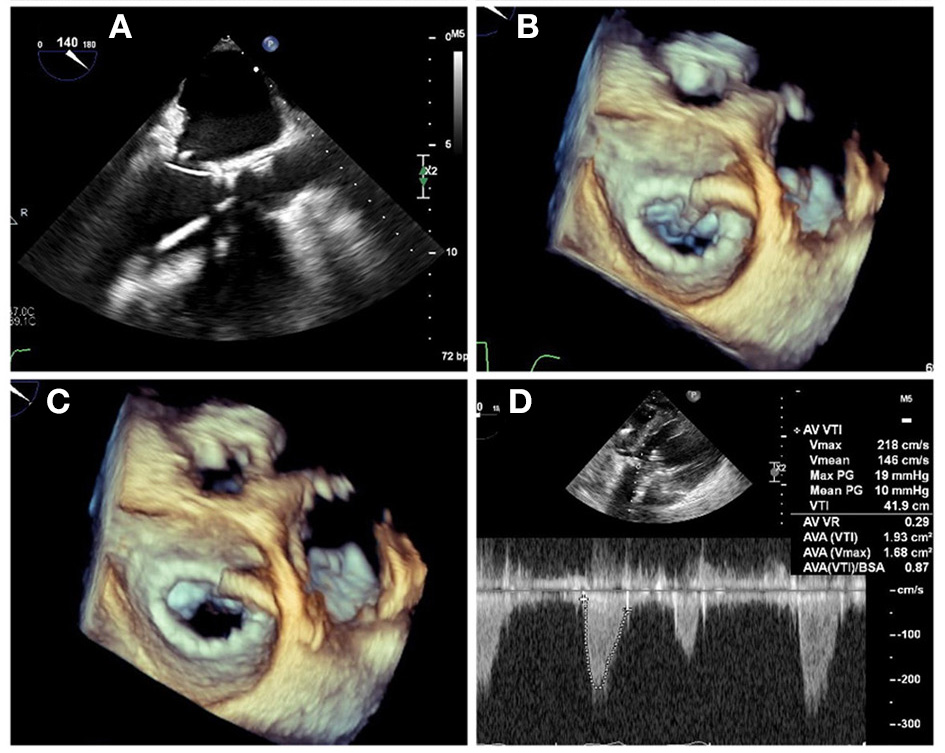

Post-deployment Assessment

Immediately after device delivery, a careful TEE evaluation should be performed, aimed at assessing the device position and morphology, hemodynamic changes, presence of valvular or paravalvular regurgitation, LVOTo, and excluding complications such as new pericardial effusion or wall motion abnormalities (Figure 10). Attention should be given to the lateral wall of the LV, atrioventricular groove, circumflex artery, and coronary sinus since trauma and rupture can occur as a result of device deployment and should be promptly recognized. The new valve should be well-seated in the intended position, without evidence for rocking motion (Supplementary Video 3). The valve leaflets should appear pliable with normal motion and laminar flow by Doppler evaluation. Trans-mitral gradients should be again assessed and compared with baseline. PVL can occur when the THV frame is not perfectly apposed against the native annulus, ring, or existing bioprosthesis and should be carefully assessed by 2D and 3D color Doppler interrogation, as previously discussed. As PVL jets can often be multiple and eccentric, 3D color Doppler evaluation is very helpful in the characterization of jet location and direction, as well as quantification by measurement of the vena contracta area in 3D MPR, which requires proper technique ensuring adequate spatial and temporal resolution. Additionally, the pulmonary vein flow should be assessed bilaterally, and systolic antegrade flow should be confirmed. Moderate or greater degree of PVL is associated with adverse outcomes and may require repeat balloon inflation or percutaneous closure with an occluder device prior to finalizing the procedure.

Figure 10

Post TMVR assessment immediately after deployment. (A) 3D color Doppler evaluation from an en-face surgeon's view immediately after a valve in MAC implantation reveals two areas of paravalvular leak (PVL) at 10 and 1 o'clock (yellow arrows). See Supplementary Video 3 for 3D en face evaluation of valve morphology and leaflet motion. (B) Careful interrogation of the largest area of PVL with 3D MPR reveals a vena contracta area of 0.12 cm2. (C) Pulsed-wave Doppler interrogation of the LVOT from a transgastric view in order to exclude a significant gradient or obstruction. (D) Evaluation of residual iatrogenic septal defect size and direction of flow.